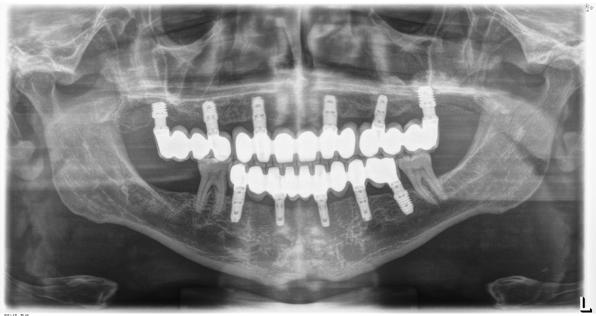

En la radiografía panorámica se observaron 28 dientes permanentes erupcionados y los gérmenes de los terceros molares, la longitud radicular es de 2:1; los senos, cóndilos y ramas mandibulares son simétricas, no presenta patologías (Figura 3).

Figura 3. Radiografía panorámica inicial.

Figura 3. Radiografía panorámica del paciente donde observamos la pérdida ósea ocasionada por la periodontitis agresiva y los dientes que se encuentran con el único sostén de los tejidos gingivales como los del frente anterior. Además, vemos cómo los molares de ambos cuadrantes superiores deben ser extraídos por presentar un mal pronóstico desde el punto de vista periodontal y restaurador.

cómo existen varias piezas dentales con pronóstico dudoso con grandes caries con afectación radicular que deben ser extraídas, como los molares de los sectores posteriores maxilares, tanto derecho como izquierdo (Figura 3).